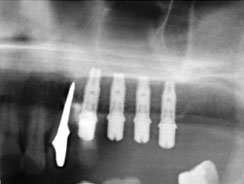

Имплантация